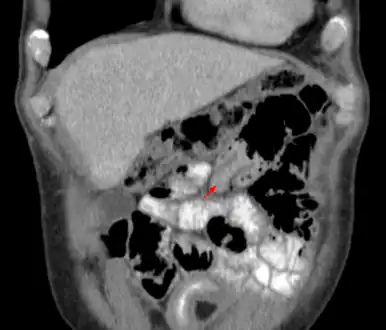

An intussusception is often suspected based on history and physical exam, including observation of Dance's sign. A digital rectal examination is particularly helpful in children, as part of the intussusceptum may be felt by the finger. A definite diagnosis often requires confirmation by diagnostic imaging modalities. Ultrasound is the imaging modality of choice for diagnosis and exclusion of intussusception, due to its high accuracy and lack of radiation. The appearance of target sign (also called "doughnut sign" on a sonograph, usually around 3 cm in diameter, confirms the diagnosis. The image seen on transverse sonography or computed tomography is that of a doughnut shape, created by the hyperechoic central core of bowel and mesentery surrounded by the hypoechoic outer edematous bowel.[8] In longitudinal imaging, intussusception resembles a sandwich.[8] It is also called "pseudokidney" sign because hyperechoic tubular centre is covered by a hypoechoic rim producing a kidney-like appearance.[9]

Small intestinal invagination on computed tomography -